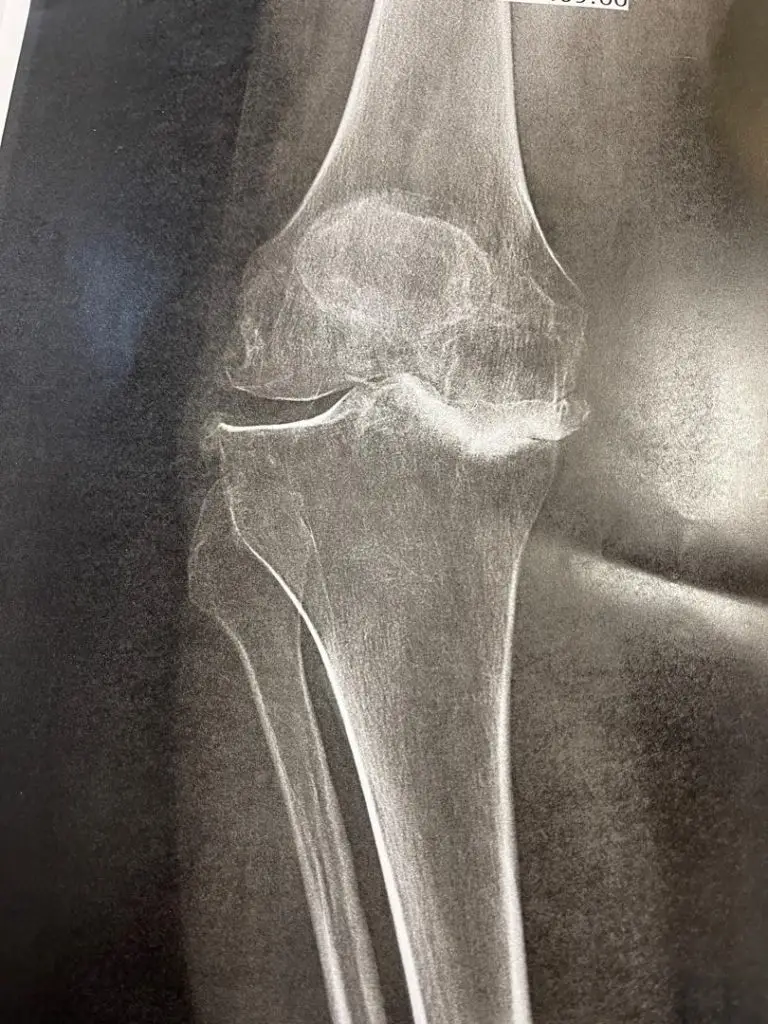

تعویض مفصل زانو یا Total Knee Replacement (TKR) که با نام آرتروپلاستی زانو نیز شناخته میشود، یکی از موفقترین جراحیهای ارتوپدی در سراسر دنیاست.

در این عمل، بخشهای آسیبدیده از مفصل زانو (غضروف و استخوانهای ساییدهشده) با قطعات مصنوعی از جنس فلز، سرامیک یا پلاستیکهای مخصوص جایگزین میشوند.

این عمل معمولاً برای افرادی توصیه میشود که به آرتروز پیشرفته، تغییر شکل زانو (مثل زانو پرانتزی یا ضربدری) یا تخریب مفصل ناشی از روماتیسم یا آسیبهای شدید دچار شدهاند.

- آرتروز پیشرفته زانو (Osteoarthritis):

زمانی که غضروف مفصل کاملاً از بین رفته و استخوانها روی هم ساییده میشوند، درد مزمن و محدودیت حرکتی شدید بروز میکند. - روماتوئید آرتریت و سایر آرتریتهای التهابی: